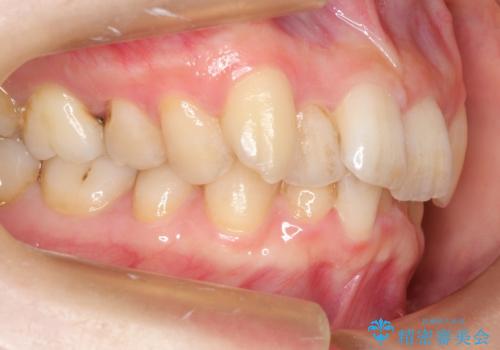

抜歯ありワイヤー矯正にて治療を行い、抜歯する歯に関しては虫歯で抜歯が必要な部分を有効活用することで、健康な歯を保存するように努めました。

噛み合わせが深い過蓋咬合という状態でもあったため、下の歯の装置をつけたり、嚙み合わせを上げる(下の歯が見える状態にする)ことにたいへんに苦労した症例でした。